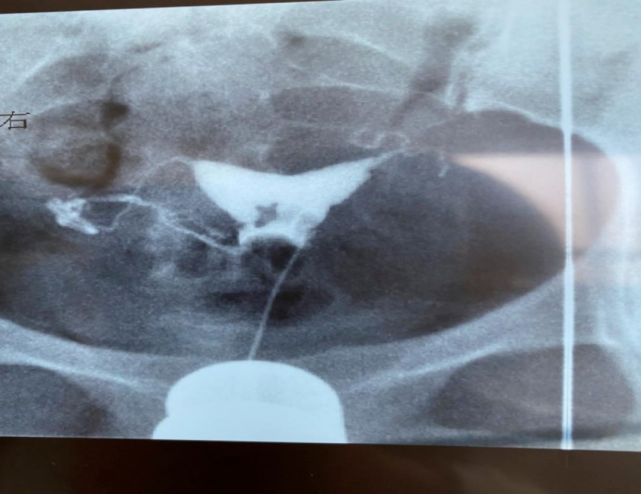

2. 子宫输卵管造影(HSG)检测 IUA 的敏感性为 75%~81%,特异性为 80%,阳性预测值为 50%,但假阳性率高达 39%,且不能检测到子宫内膜纤维化或 IUA 的性质和程度,可作为筛查实验。

图片

图源:作者提供